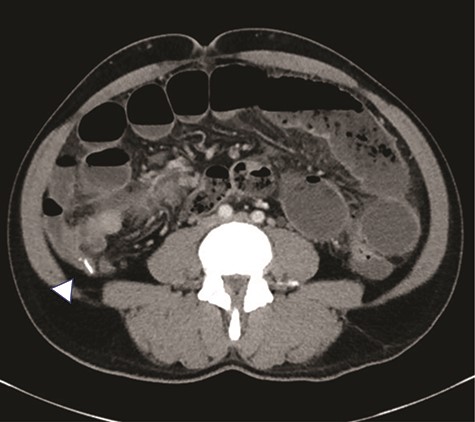

A 47-year-old male presented to the Emergency Department with abdominal pain, nausea, emesis and diarrhea for four days. His last bowel movement was the day prior and he was continuing to pass flatus. On physical examination, his abdomen was soft and nondistended, with tenderness in the epigastrium and left lower quadrant. His vital signs and laboratory values were within normal limits. Computerized topography (CT) scan showed a high-grade SBO with a transition point within distal ileum with asymmetric irregular bowel wall thickening, which was suggestive of a mass (Fig. 1). A moderate amount of ascites was also noted, as well as an appendicolith within the appendix, mildly thickened to 8 mm without any other sign of inflammation (Fig. 2). The patient was admitted to the hospital for initial conservative management, and a cancer work up was initiated for a primary SBO. CT of the chest showed no distant metastases. Tumor markers (carbohydrate antigen 19–9, carcinoembryonic antigen and alpha-fetoprotein) were all within normal limits. Over the next three days, the patient regained bowel function and his pain improved. He opted for outpatient colonoscopy and surgery and was discharged home. Two days later, the patient represented to the ED with abdominal pain, distention and emesis. He had a normal white blood cell count with neutrophilia and lactic acidosis of 3.1. A repeat CT scan of the abdomen and pelvis showed essentially unchanged findings from the prior study. He then was taken to the operating room for exploratory laparotomy. A firm mass was noted 20 cm proximal to the terminal ileum with a mass lesion and an abnormal, firm appendix. We performed a small bowel resection and appendectomy. The patient was subsequently referred to the hematology/oncology department for further treatment. He underwent a bone marrow biopsy which was negative for evidence of leukemia and subsequently began treatment with induction chemotherapy.

High grade SBO with a transition point within the right lower quadrant in distal ileum (arrow). The bowel loop in this region demonstrates significantly asymmetric irregular wall thickening (arrowhead).